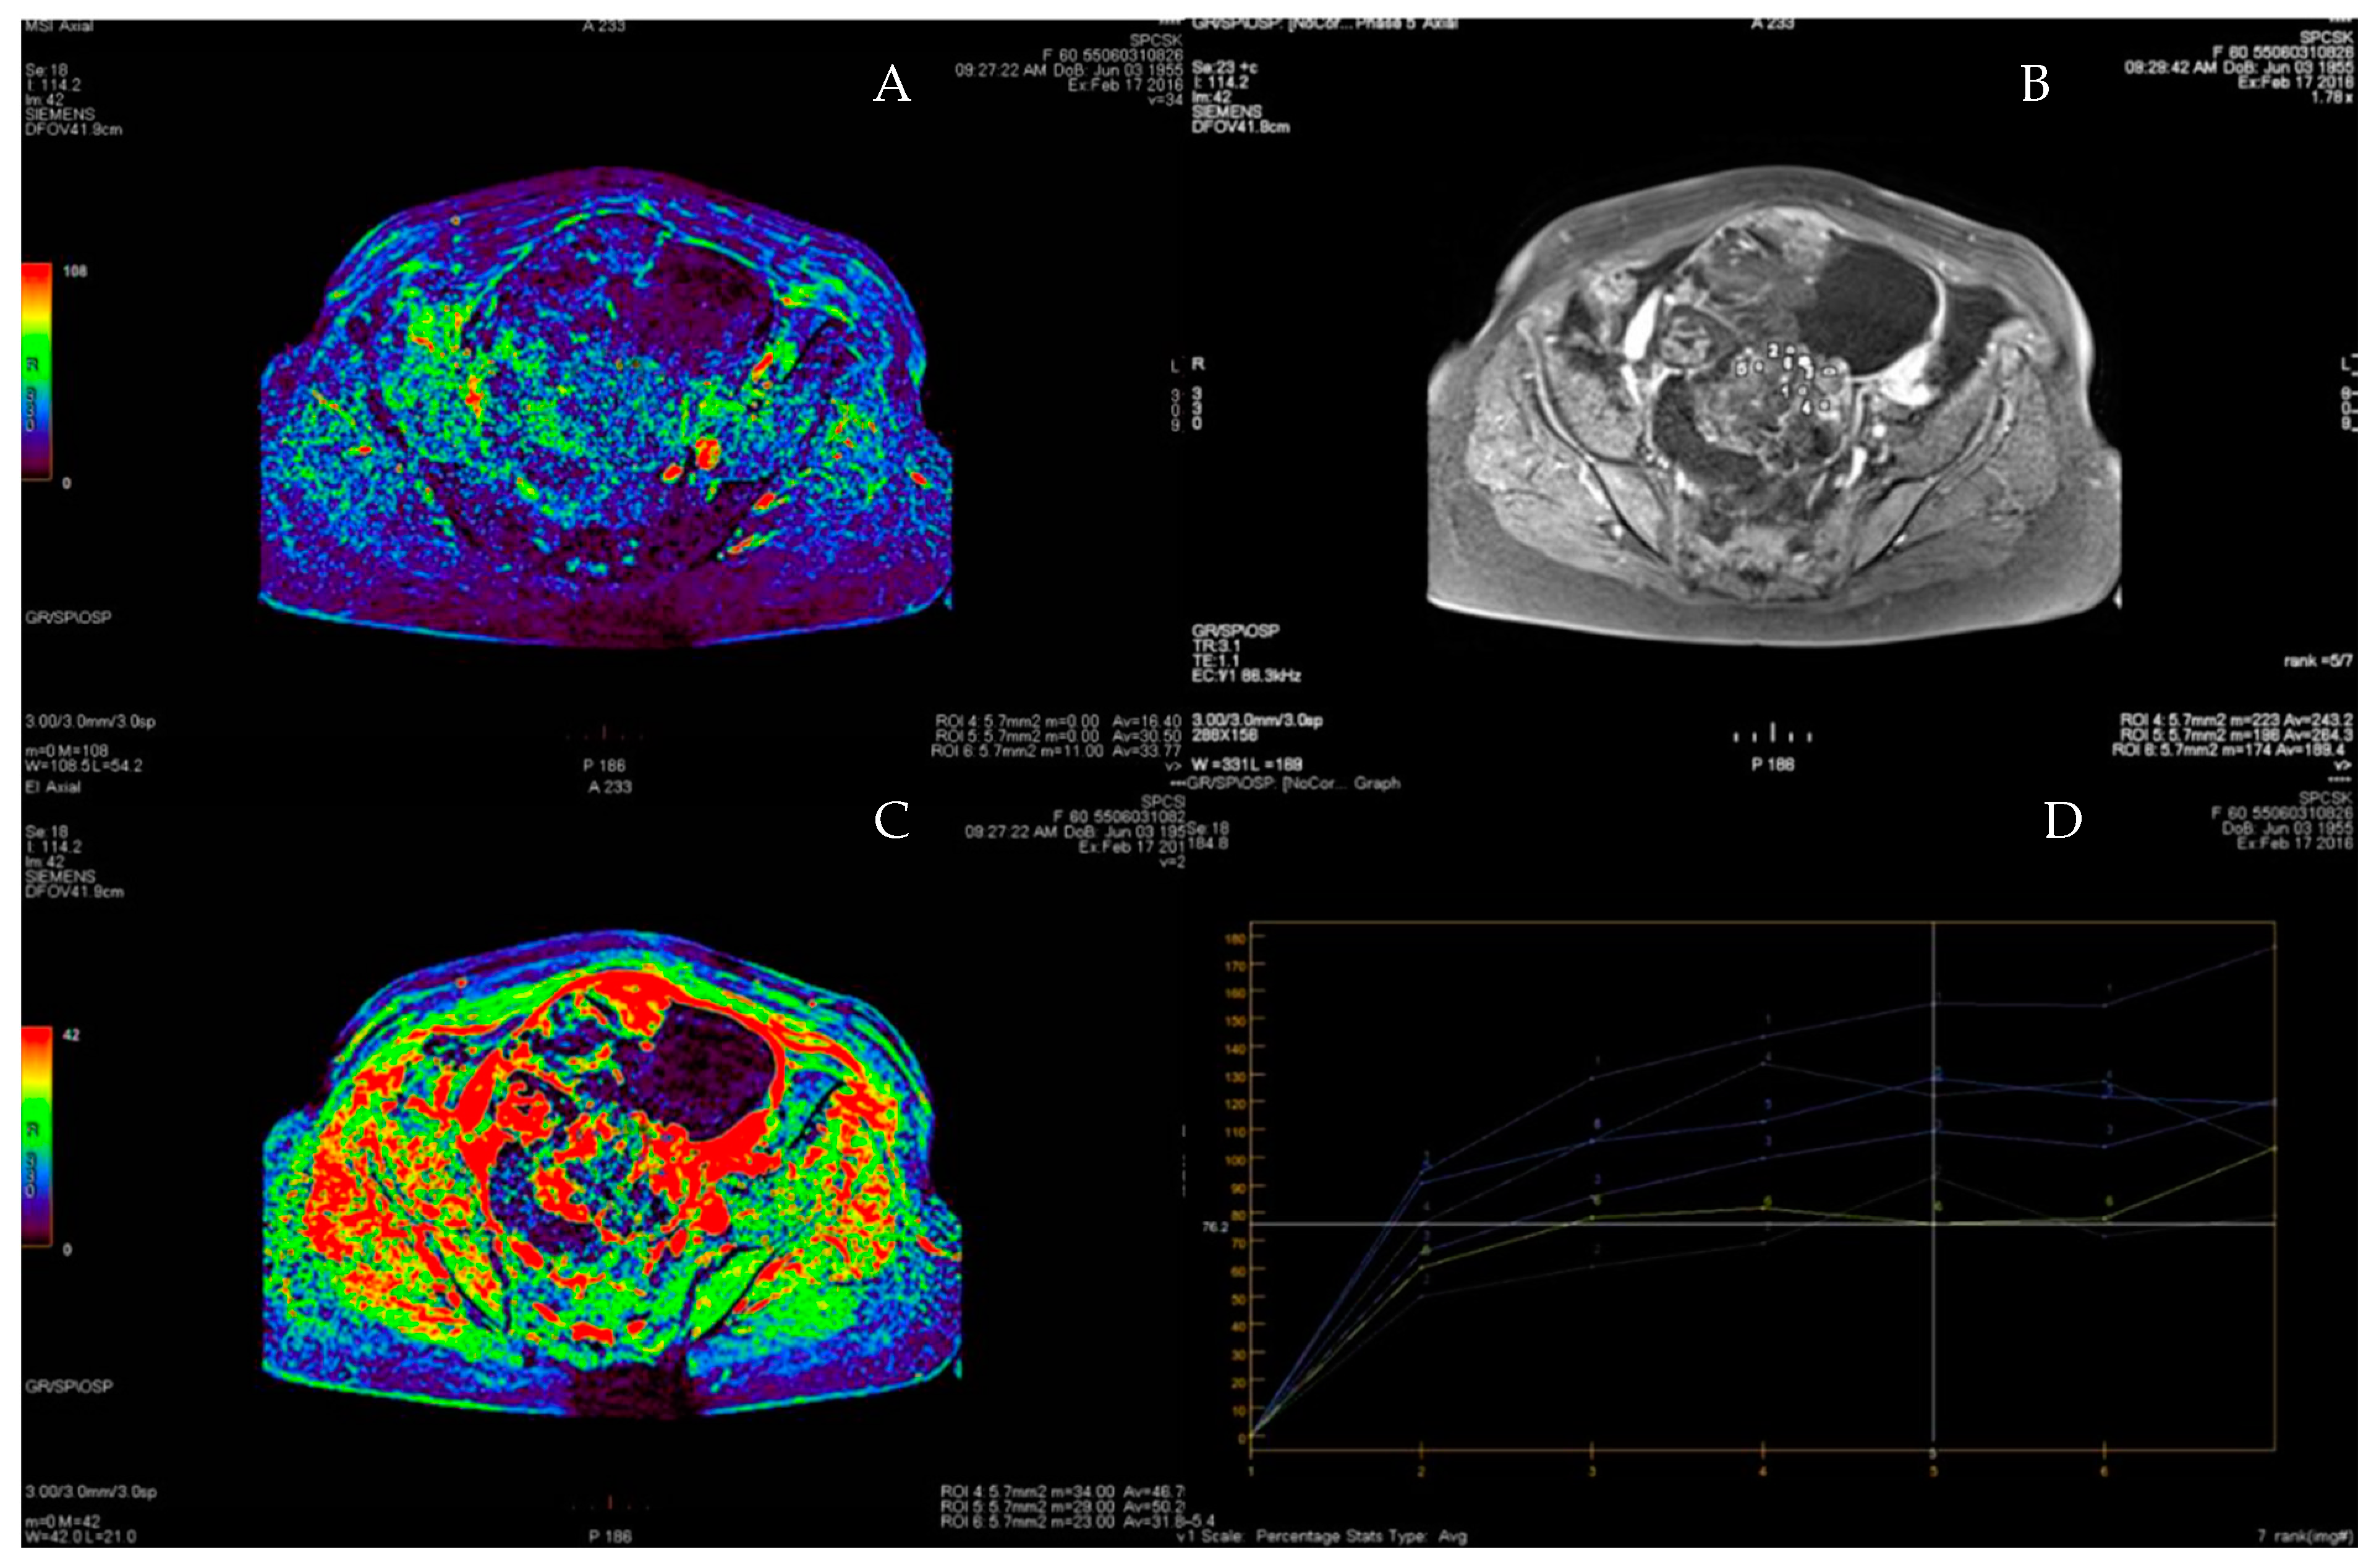

3.4. ROC Curve for LGSC vs. MOC

3.5. ROC Curve for HGSC vs. MOC